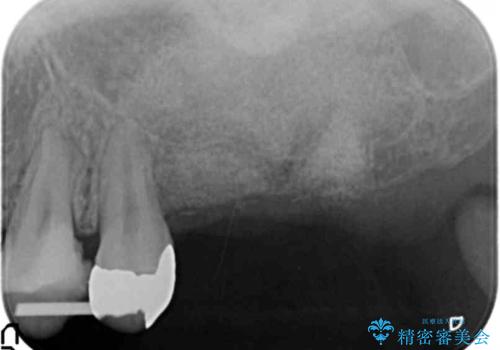

X線検査の結果、左上6には歯根破折、左上7には銀歯の下に大きな虫歯の再発が認められ共に抜歯をせずには症状の改善が見込めない状況です。

奥歯を2本失ったのち、しっかりと噛める環境へと整備するため、しっかりと骨の造成を行い清掃性を高めたインプラント治療を行っていくこととしました。